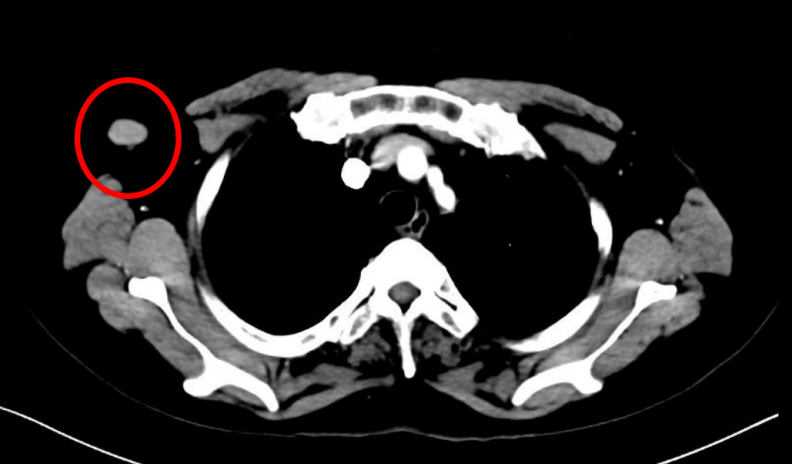

患者为女性,60岁,已绝经,既往史无特殊。2021年5月10日于院内行乳腺及淋巴结彩超检查,提示右乳腺实性结节(BI-RADS 4C级)及右腋下肿大淋巴结。进一步影像学评估显示,右乳原发灶大小约2.7×2.3 cm,右腋窝淋巴结约1.8×1.3 cm;同时可见双肺结节,最大约0.9×0.7 cm,并见右肺门淋巴结约1.1×1.0 cm。整体影像学结果提示患者初诊时已存在乳腺原发灶伴区域淋巴结及肺部转移。

图1:右乳腺肿物